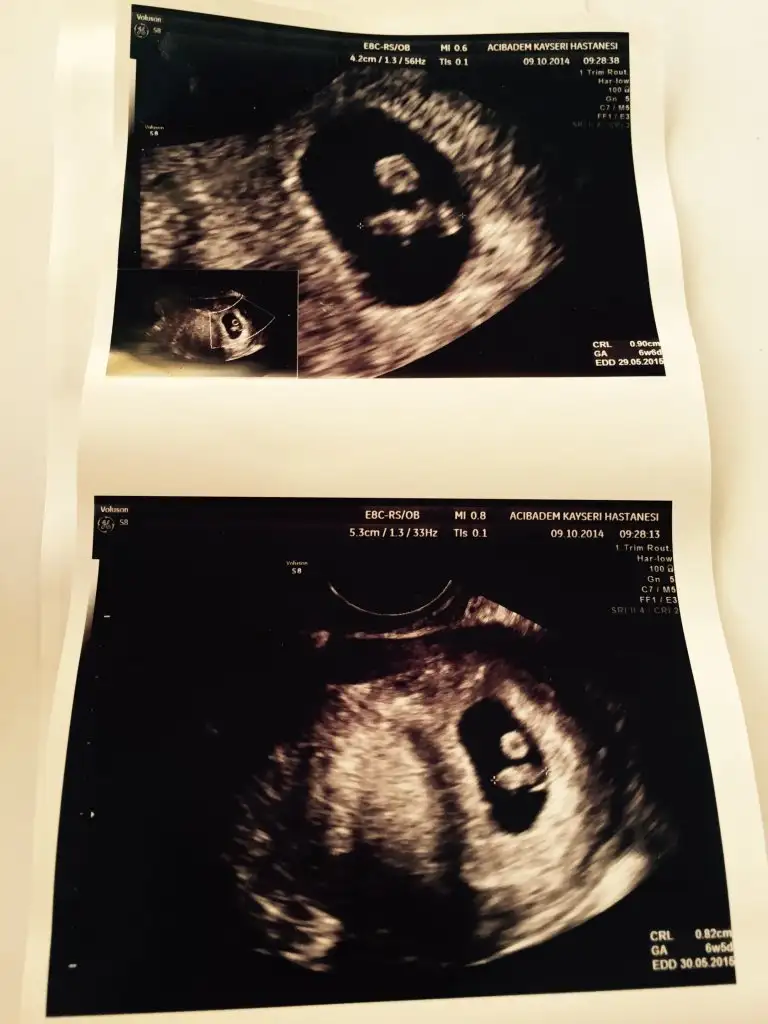

benim bebeğimde ilk başta uzun fasulye gibiydi ve denildiği gibi ultrasonda solda karnımda sağda idi. şimdi nub teorisine göre kesin kız ve artık ortaya geçmiş bende şaşırdım artık kesin desin doktorum istiyorum